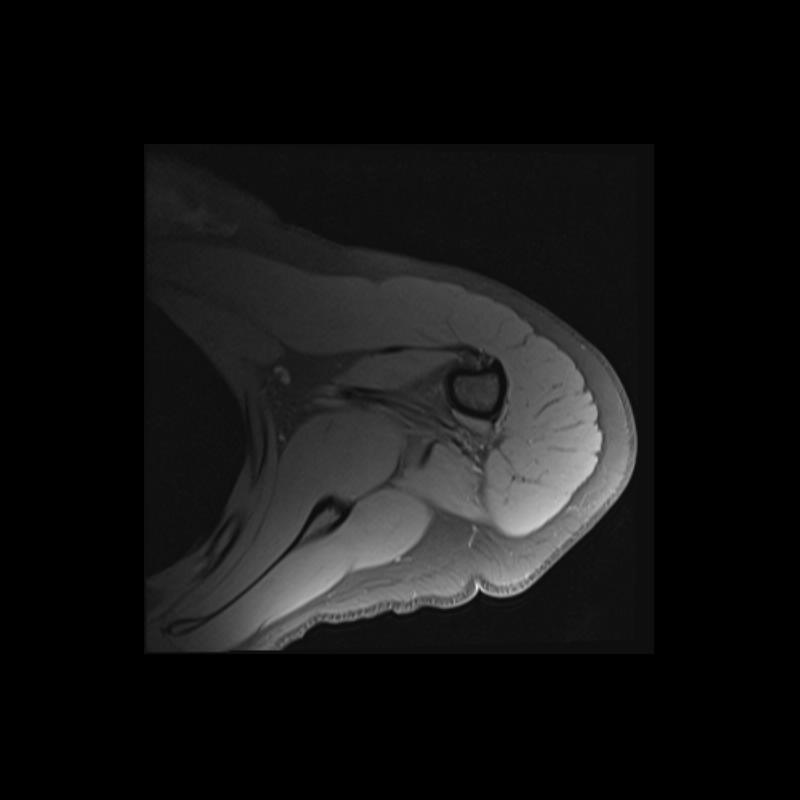

Shoulder MRI Anatomy